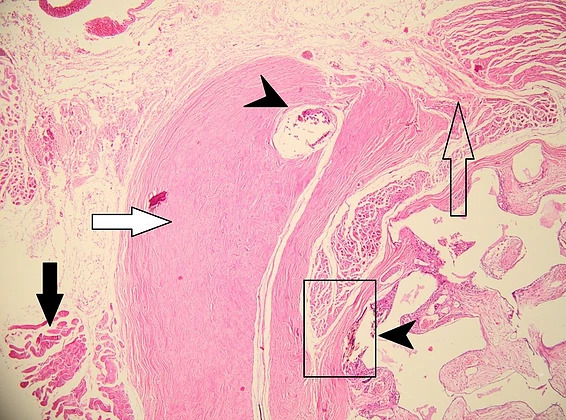

The histolopathological analysis performed shows in the meshes of the prosthetic material, fibrovascular tissue and minimal polymorphic inflammatory infiltrate (lymphocytes, plasma cells and polymorphonuclear neutrophils) and moderately frequent multinucleated giant cells of the “foreign body” type at the interface with the hydroxyapatite as well as osteoclasts at the interface with the hydroxyapatite nanocomposite material. At different levels in the muscle tissue and in the corresponding sclera, amorphous, acellular material (mono and multifilament surgical threads) bordered by multinucleated giant cells of the “foreign body” type is observed. (Figure 11,12). It can be observed that the invasion of the implant with fibrovascular material begins from the incision and the initial suture area, and the presence of multinucleated giant cells of the foreign body type in not very large numbers attests to good compatibility, at least equal to that of the suture material.

Figure 11: Histopathological appearance of the hydroxyapatite implant in hematoxylin-eosin (HE) staining – subject 1. The following structures are depicted: black arrow – striated muscle, white arrow – remnant sclera, empty arrow – incision site, arrowhead – surgical threads. Proliferation of fibrovascular tissue is observed inside the implant starting from the incision and suture site with uniform distribution through the nanostructured hydroxyapatite material (observed as white-gray areas marked by blue arrows). The fibrovascular tissue present attests to the complete vascularization of the implant 2 months after implantation with good tolerability.